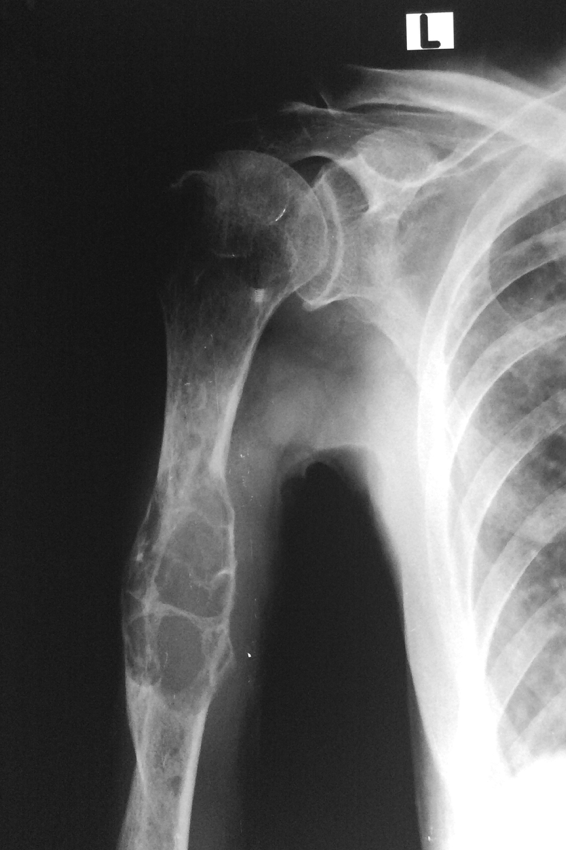

Blowout METs on X-ray

Multiple Myeloma in proximal humerus on X-ray